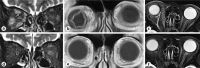

We report a case of idiopathic orbital inflammation with a shallow anterior chamber and choroidal detachments. This study involved an 87-year-old female patient who presented at our department after becoming aware of the progression of diplopia. Examination of the patient's right eye revealed proptosis, as well as conjunctival edema with dilated and tortuous blood vessels. The right-eye anterior chamber was shallow, and fundus examination revealed marked choroidal detachments. Magnetic resonance imaging revealed enlargement of the right-orbit extraocular muscles and a suspected compression of the right-orbit superior and inferior ophthalmic veins, yet no expansion of the cavernous sinus. We diagnosed the patient as having idiopathic orbital inflammation in her right orbit, and subsequently started corticosteroid therapy. One week after initiating treatment, the anterior chamber was found to be nearing a normal depth, and the choroidal detachments were found to have disappeared. Our findings revealed that the inflammatory swelling of the extraocular muscle due to idiopathic orbital inflammation resulted in compression of the right-orbit superior and inferior ophthalmic veins, thus leading to an apparent choroidal circulation disorder that presented with a shallow anterior chamber and marked choroidal detachments.